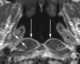

Enlarged adenoids

Adenoid hypertrophy (enlarged adenoids) is the unusual growth (hypertrophy) of the adenoid (pharyngeal tonsil) first described in 1868 by the Danish physician Wilhelm Meyer (1824–1895) in Copenhagen. He described a long term adenoid hypertrophy that will cause an obstruction of the nasal airways. [Source: Wikipedia ]